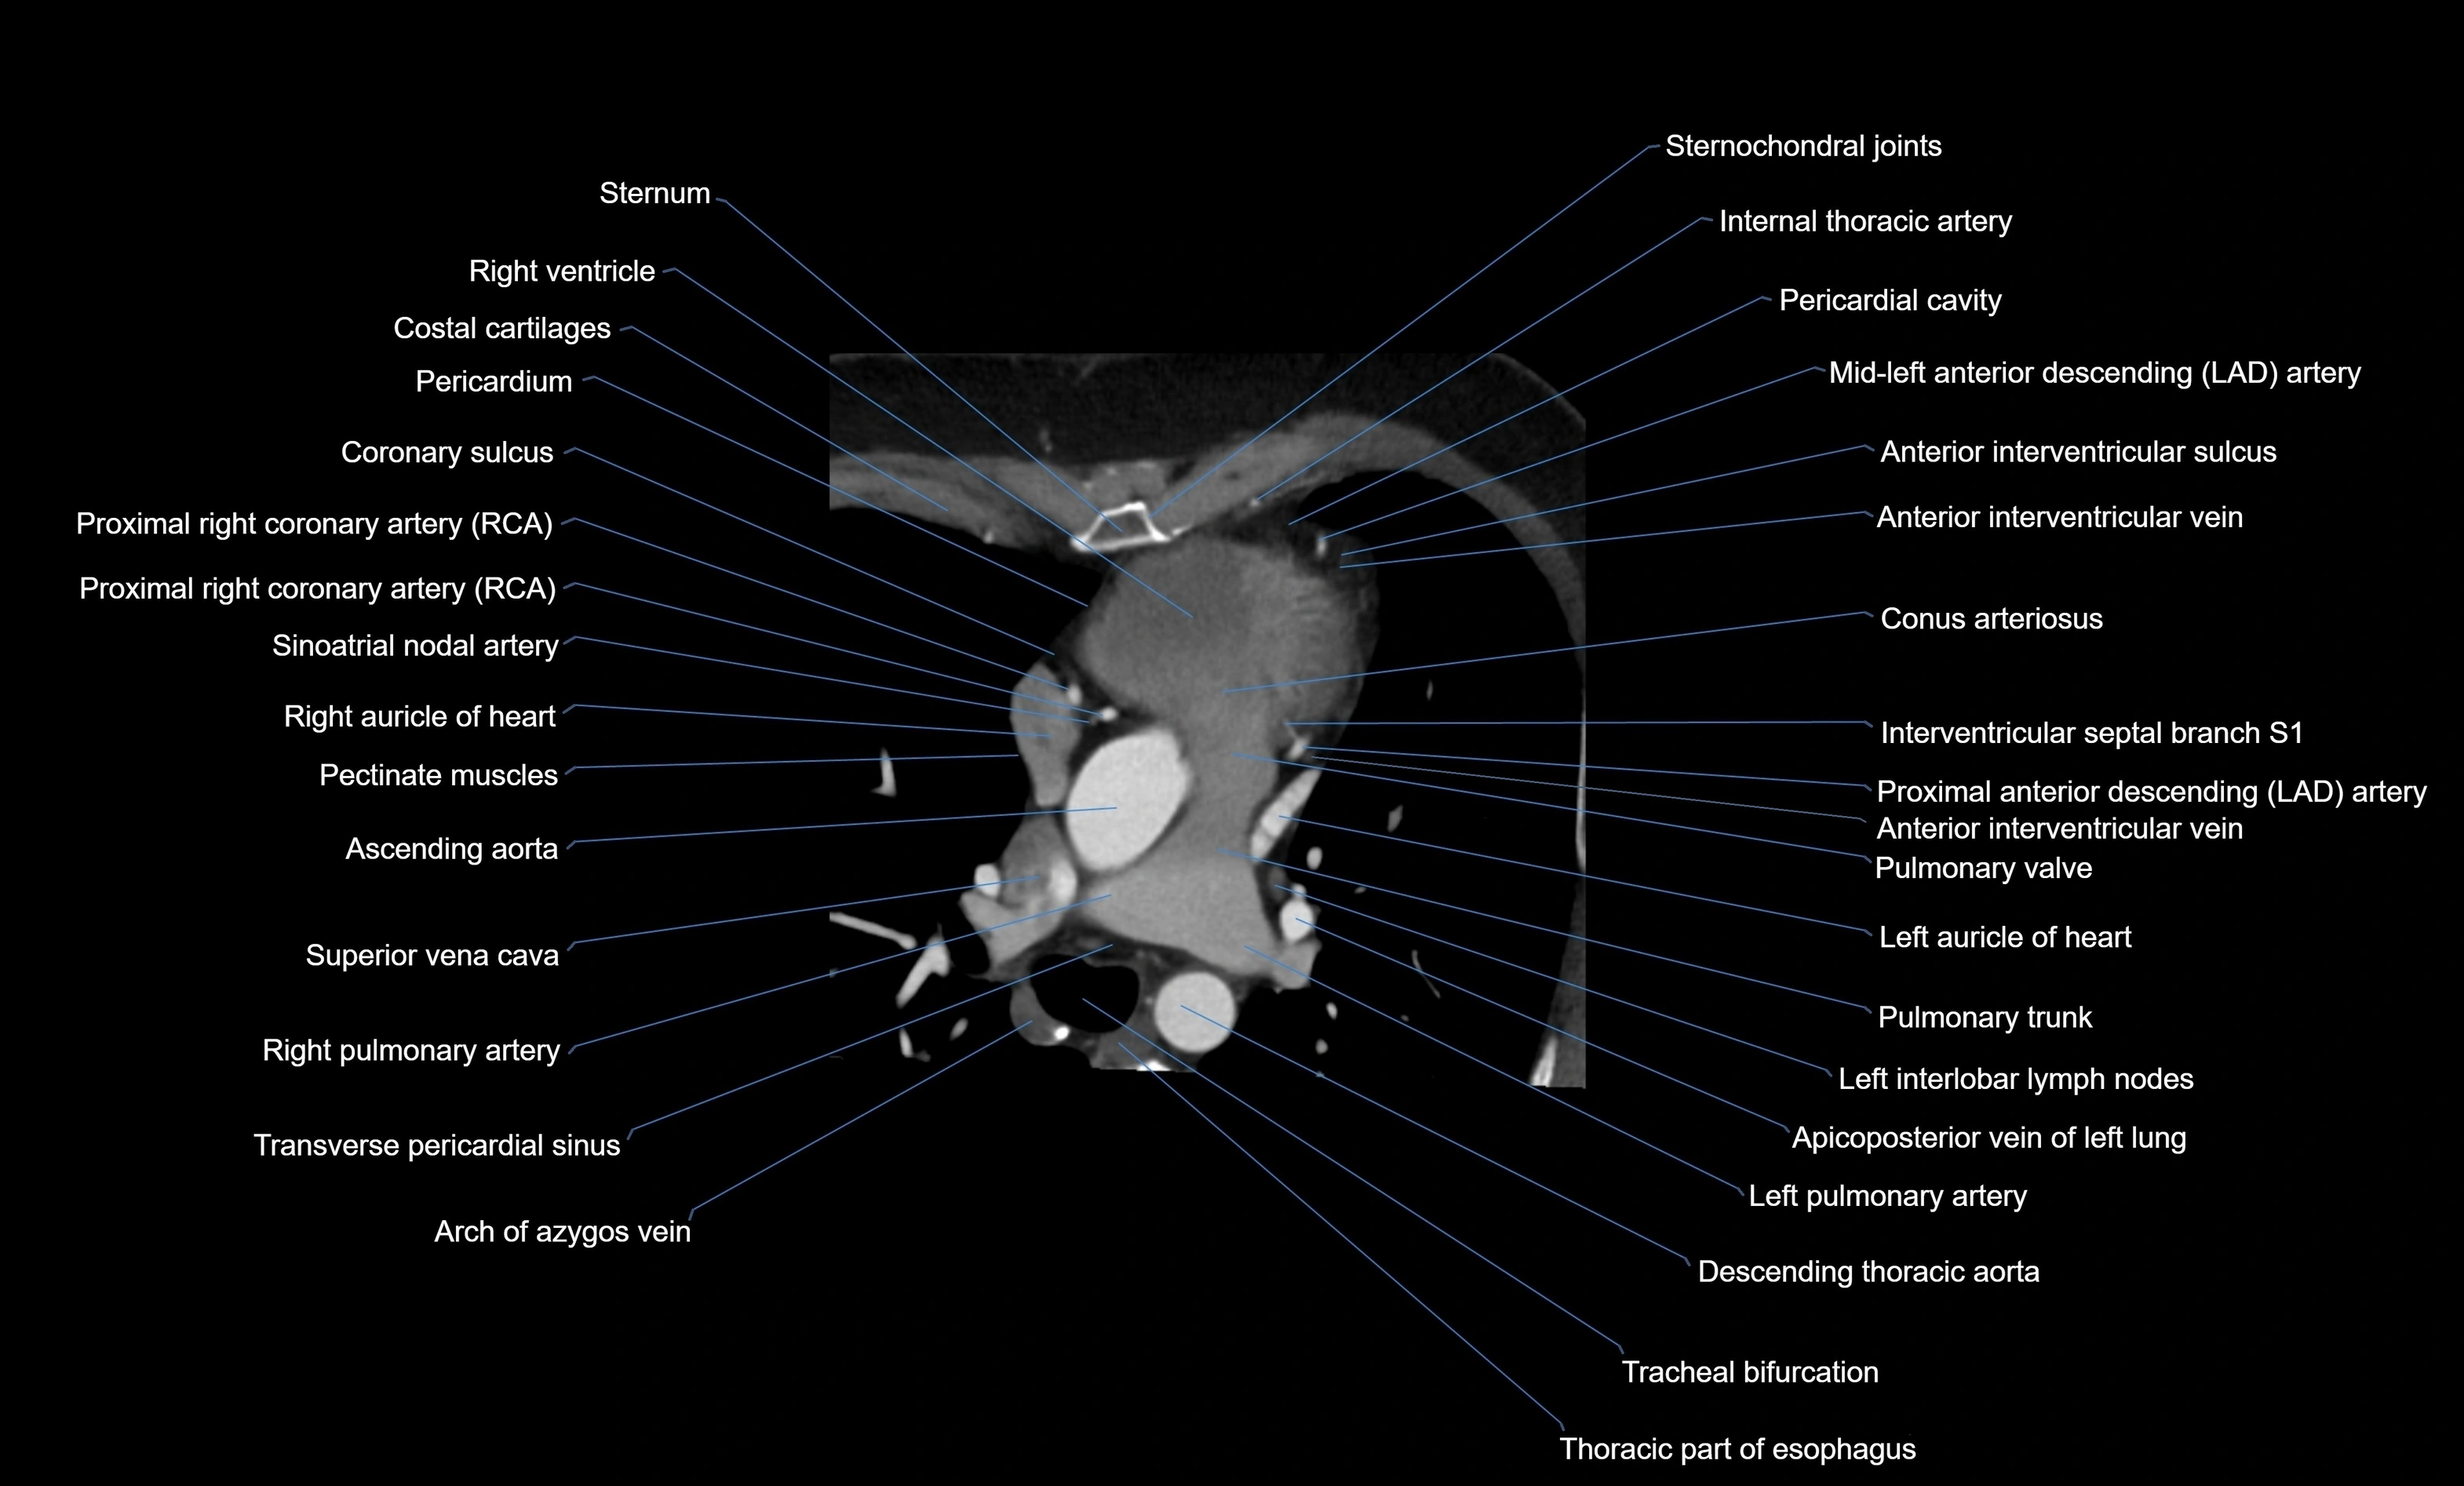

CT Appearance

CT Coronary Angiography (CCTA):

-

Best non-invasive modality for acute marginal artery visualization

Shows origin, course along the acute margin, and right ventricular branches

Detects stenosis, occlusion, calcified and non-calcified plaques, aneurysm, or anomalous course

Multiplanar reformats and 3D reconstructions help in pre-PCI and surgical planning

Critical for assessing right ventricular infarction risk in RCA disease

MRI image

CT images